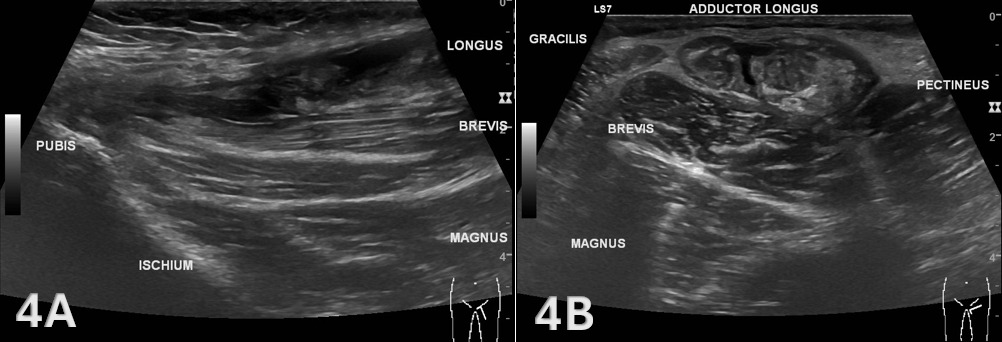

Figure 4. Adductor Longus Tear (LAX and SAX)

Figures 4A and 4B demonstrate a complete non-bony avulsion of the adductor longus tendon from its pubic attachment, with approximately 32 mm of tendon retraction and an intervening fluid-filled defect consistent with acute hematoma or edema. The retracted tendon end appears thickened and oedematous, indicative of acute injury. The adductor brevis, adductor magnus, gracilis, and pectineus muscles demonstrate normal echotexture and continuity, confirming that the injury is isolated to the adductor longus.11